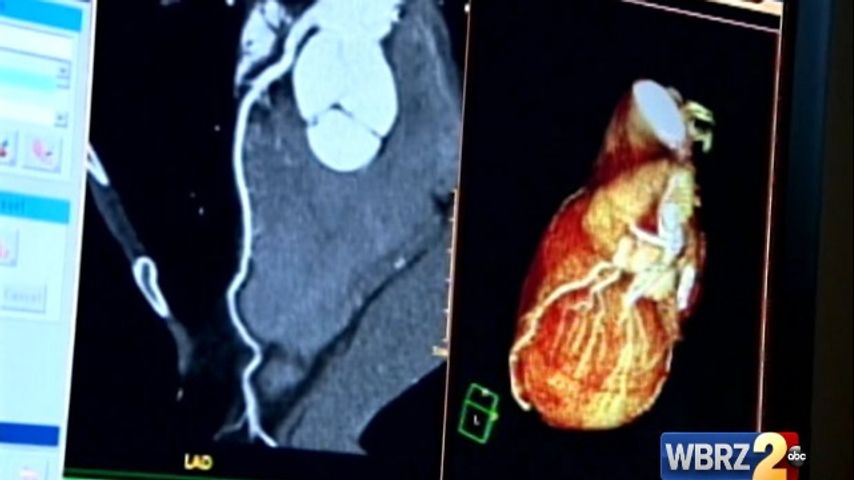

BATON ROUGE- Today is a day dedicated to spreading awareness for the number one killer of women in the capital area, heart disease.

According to a release, heart disease is the number one killer of women ages 20 and over, taking the life of one in four women each year.